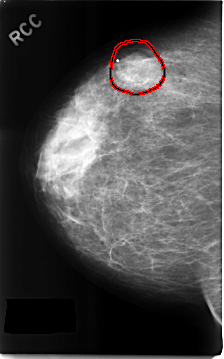

C_0313_1.RIGHT_CC

FILE: C_0313_1.RIGHT_CC.OVERLAY

TOTAL_ABNORMALITIES 1

ABNORMALITY 1

LESION_TYPE MASS SHAPE LOBULATED MARGINS OBSCURED

ASSESSMENT 4

SUBTLETY 4

PATHOLOGY BENIGN

TOTAL_OUTLINES 1

BOUNDARY